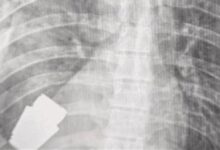

انتبهوا.. هذه الأعراض المألوفة تنذر بسرطان الرئة!

ووفقا لـ”Macmillan Cancer Support” يحدث تورم الوجه عندما يضغط الورم على الوريد الأجوف العلوي (SVC)، الذي يربط الرأس بالقلب، إذ يشير الأطباء إلى أن أغلب حالات انسداد الوريد الأجوف العلوي (SVCO) ناتجة عن سرطان الرئة.

ولفت الأطباء إلى أن معظم حالات انسداد الوريد الأجوف العلوي ناتجة عن سرطان الرئة أو انتشار المرض إلى الغدد الليمفاوية القريبة، بحيث تصبح منتفخة.